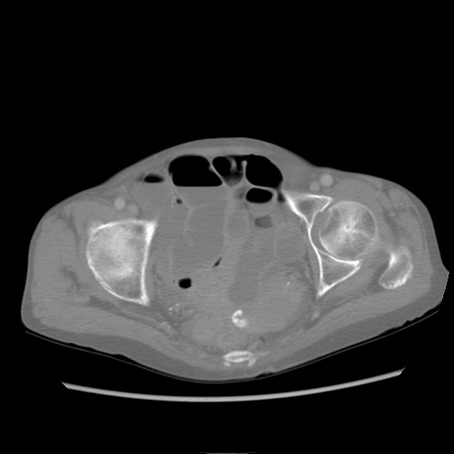

症例25(横断像)

症例

【症例】80歳代女性

【主訴】胸のつかえ感

【現病歴】約9時間前に食後から胸のつかえた感じあり、嘔吐あり、来院。

【既往歴】胃癌(全摘)、胆摘、虫垂炎

【身体所見】心窩部に圧痛あり、反跳痛なし。

【データ】WBC 5700、CRP 0.05